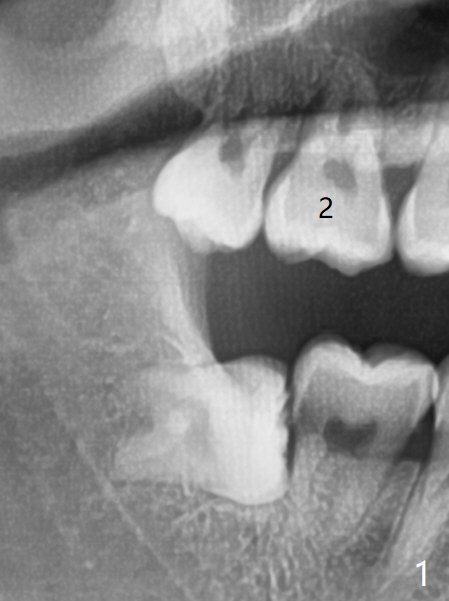

A 19-year-old man with mental retardation returns to clinic for extraction of the 3rd molars in 2 visits (Fig.1,2). The sockets heal without delay (Fig.3,4).